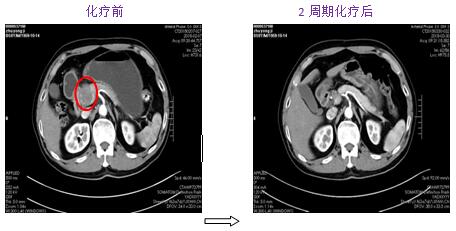

針對(duì)每一例化療患者,參照最新NCCN指南(為腫瘤診療的國(guó)際權(quán)威指南),為患者制定規(guī)范、有效的個(gè)體化化療方案。2周期化療后評(píng)價(jià)療效:其中1例肺癌肉瘤術(shù)后的胰腺占位的患者,2次化療后胰腺占位基本消失,另有1例非小細(xì)胞肺癌伴肺、心包、肝多發(fā)轉(zhuǎn)移患者,2次化療后肺部、肝內(nèi)病灶顯著縮小,其余化療患者還未到療效評(píng)價(jià)時(shí)機(jī)(指南推薦每2周期評(píng)價(jià)化療療效)。

圖1. 2周期化療后胰腺區(qū)占位基本消失